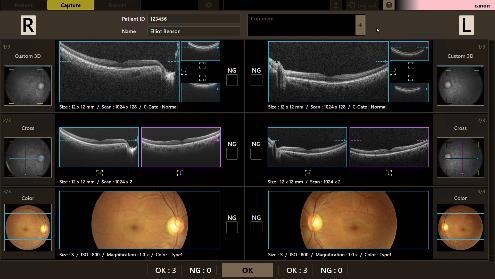

⚫“OCT-R1”と“CR-10”はいずれも、新たに開発したタッチパネル式のユーザーインターフェースを搭載。眼が写った画面をタッチするだけで、装置が撮影位置の調整を自動で行い、撮影中の眼の動きを自動で追尾し、撮影するオート撮影※が可能。

⚫タッチパネルを用いた簡単な操作で、左右の眼の撮影から検査結果の一覧表示までを自動で行うことができるため、撮影者のスキルに頼らず撮影が可能。さらに、撮影に失敗した画像を自動判定し、確認画面に表示。再撮影をワンタッチで簡単に行うことも可能。

⚫“OCT-R1”は、OCT断層像とカラー眼底写真を一度のワンタッチ操作で撮影が可能。OCTにおいては従来機種上回るスキャン幅約14.7mm、深さ約13.4mm の広画角撮影を実現。広範囲を一度の撮影で高精細に画像化できるため、病変の早期発見などに貢献。

⚫高画質なOCT の断層像により、脈絡膜から網膜、硝子体の状態を観察することが可能。眼科系疾患の診断・治療方針の決定などに貢献。

⚫眼底の三次元画像から画像処理技術を用いて血管形態を抽出するOCTAの撮影が可能。AIによるノイズ低減処理機能「Intelligent denoise※」を搭載し、ノイズの少ない高画質なOCTA画像を簡単に取得することが可能。